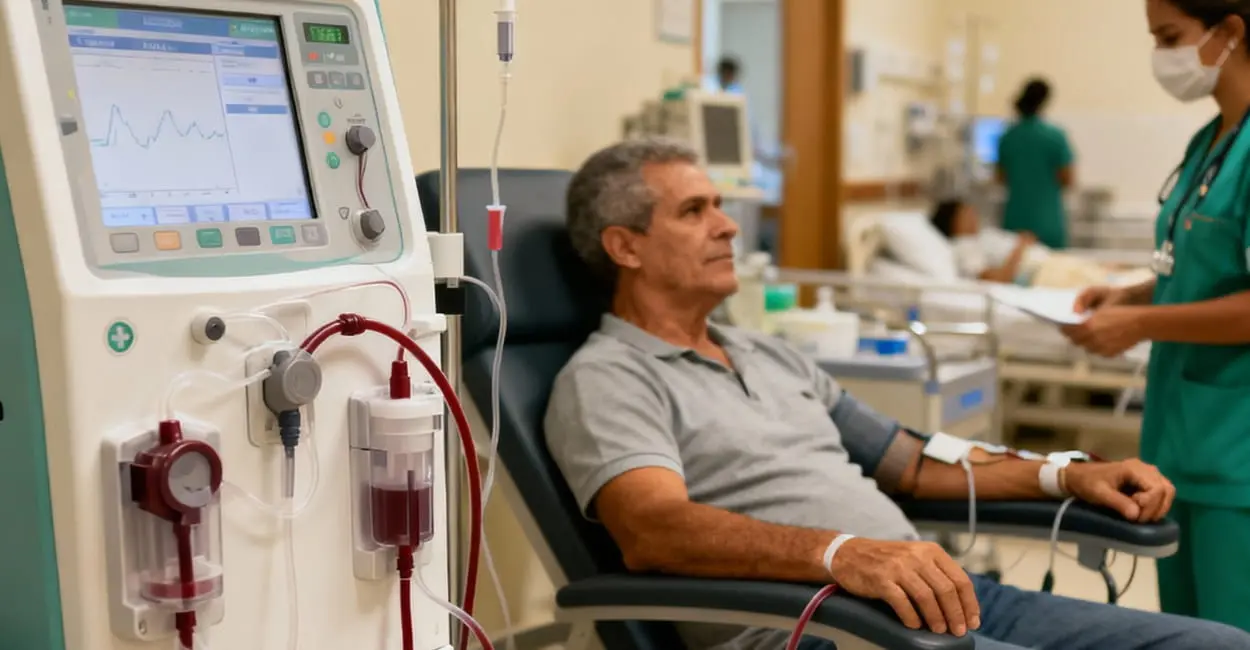

Entenda como funciona a máquina, o acesso vascular, a rotina das sessões e qualidade de vida.

Entenda em detalhes o processo de filtragem do sangue, o rim artificial e cuidados vitais.

Transforme seu tempo em diálise com atividades que ajudam na saúde mental e produtividade.